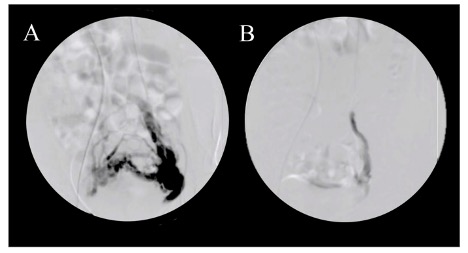

- Chụp tĩnh mạch buồng trứng ngược dòng qua ống thông qua da (chụp tĩnh mạch buồng trứng ngược dòng) cho thấy các tĩnh mạch buồng trứng ngoằn ngoèo và giãn (đường kính trên 6 mm), trào ngược tĩnh mạch và tắc nghẽn đám rối tĩnh mạch buồng trứng, và thời gian rửa trôi của chất cản quang trong khung chậu cần hơn 20 giây. Hiện nay, chụp tĩnh mạch buồng trứng ngược dòng được coi là tiêu chuẩn vàng để chẩn đoán.

- Ngoài ra chụp mạch còn là phương pháp điều trị khi có thể nút tĩnh mạch buồng trứng bằng keo sinh học và Coil.